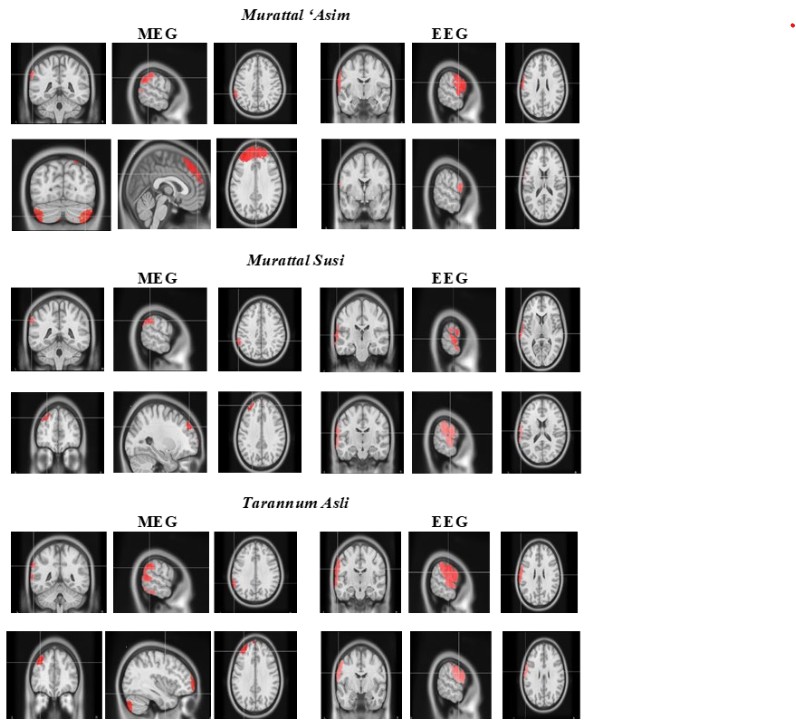

Rhythmic Quranic recitation synchronizes high-frequency gamma brainwaves across language, music, emotion, memory, and attention networks—engaging the brain similarly in Muslim and Quran-naïve non-Muslim listeners, even without understanding Arabic. neuroscirn.org/ojs/index.php/…

NeuroResNotes's tweet image. Rhythmic Quranic recitation synchronizes high-frequency gamma brainwaves across language, music, emotion, memory, and attention networks—engaging the brain similarly in Muslim and Quran-naïve non-Muslim listeners, even without understanding Arabic. neuroscirn.org/ojs/index.php/…